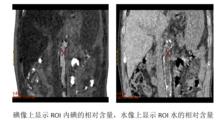

從能譜成像的原理可以得知,在能譜成像中,任何結構或組織能通過兩種基物質的組合產生相同的衰減效應來表達,即經過高、低兩組電壓掃描的X射線衰減圖像可以表達為兩種基物質的密度圖。物質分離圖像中的每一個體素反映了相應的物質密度信息,所以物質分離能獲得配對的兩組基物質密度圖。在醫學上最為常用的基物質對是水和碘,水和鈣,及鈣和碘。

多能譜CT碘像上顯示ROI內碘的相對含量,水像上顯示ROI水的相對含量

圖6 物質密度測定(圖像來源:陝西中醫學院附屬醫院)